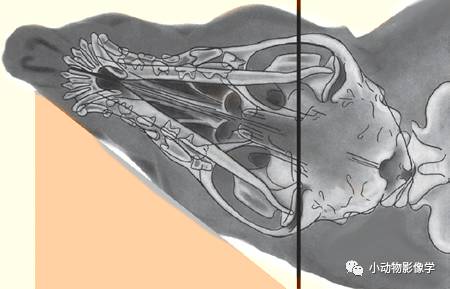

(9)颞下颌关节的拍摄

a.先拍摄标准体位DV、侧照

b.然后拍摄斜向侧照

犬:侧卧,鼻部向上或向下倾斜。一、将鼻部抬高20°,观察桌面侧颞下颌关节;二、将鼻部下压20°,使非桌面侧颞下颌关节透过对侧下颌咬肌窝投射在平板上,根据X光原理可知,这时候这一侧颞下颌关节会被放大。(参见《小动物放射诊断学》第3章)

猫:侧卧,头部向腹侧旋转20°,鼻部抬高10°,可在其它骨骼的腹侧观察到颞下颌关节。